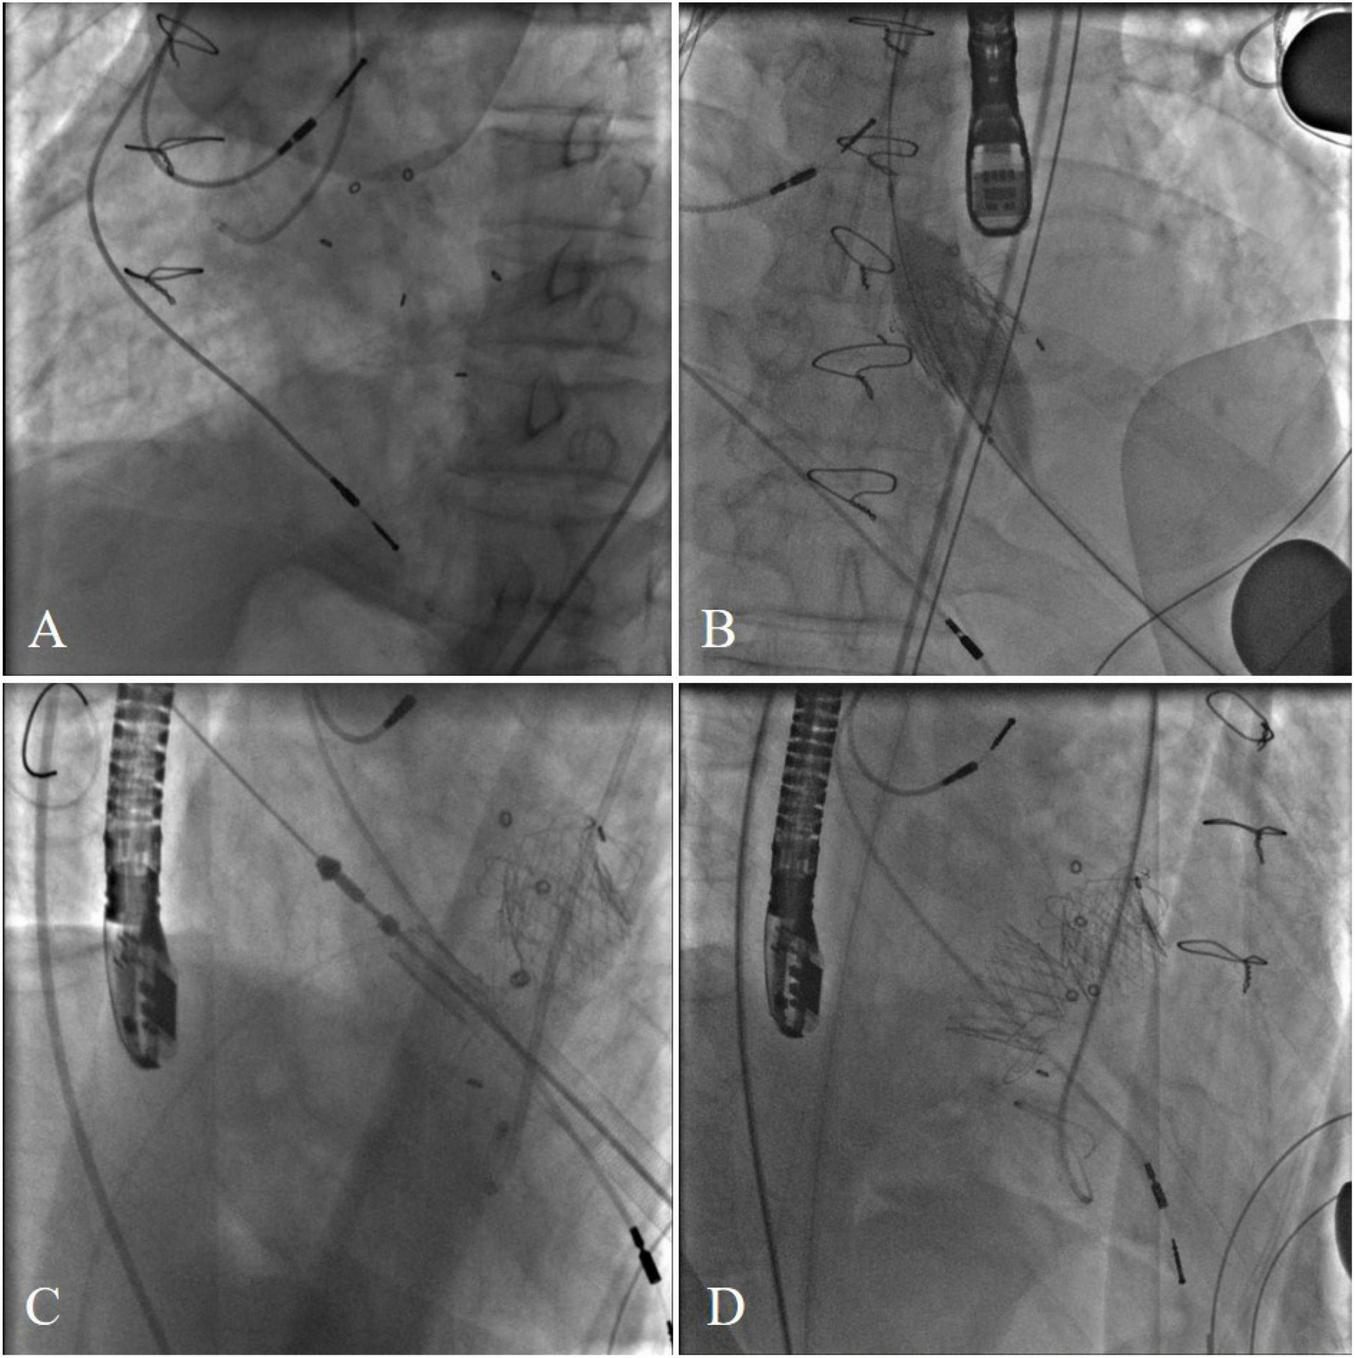

The procedure was performed in a hybrid operating room. The chest was entered in the fifth intercostal space through a small left anterolateral incision. Two pledged purse-string sutures were placed at the apex. The annulus of the Medtronic Mosaic aortic and mitral bioprosthesis was not visualized on fluoroscopy (Figure 2A). After the apical puncture, a soft guide-wire and then a super stiff guide-wire were used to cross the bioprosthetic valve and into the aorta. The J-valve delivery device was inserted. Then, a 21-mm J-valve (Jiecheng Medical Technology, Suzhou, China) was deployed in the aortic position. Transesophageal echocardiography revealed massive perivalvular leakage. Therefore, a second 21-mm J-valve was implanted in the aortic position. A total of 20 mm Atlas gold post-dilatation was used for post-dilatation in the aortic position (Figure 2B). Thereafter the super stiff guidewire was placed in the left atrium through the mitral bioprosthetic valve. The J-valve was reversely loaded on the delivery system (Figure 2C). A 25-mm J-valve was deployed under rapid pacing in the mitral position. After that, a 25 mm Newman balloon was used for post-dilation. A post-operative fluoroscopic image with both aortic and mitral VIV replacements in place was taken (Figure 2D).

FIGURE 2

(A) The annulus of the Medtronic Mosaic aortic and mitral bioprosthesis was not visualized on fluoroscopy. (B) A total of 20 mm Atlas gold post-dilatation was used for post-dilatation in the aortic position. (C) Transcatheter bioprosthetic mitral valve implantation. (D) Final cardiac fluoroscopy showing both valves deployed and seated well.